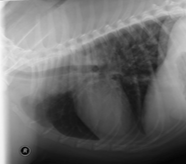

Canine Chronic Bronchitis

» Photos